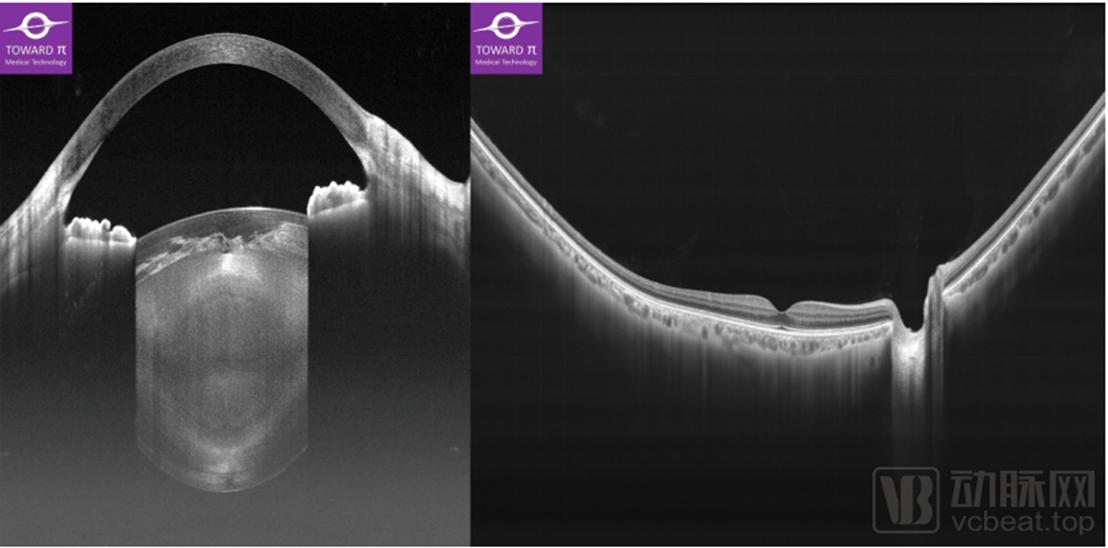

“ 瑶光·星”是图湃医疗的主流级OCT产品,不同于“北溟·鲲”的超高性能,“瑶光·星”则是主打“一台OCT,满足所有临床诊断需求”的“全景前后节一体”功能。“瑶光·星”具备10万次扫描速度,而成像深度则达到14mm,这也是目前为止眼科OCT领域的最大成像深度。该深度使得“瑶光·星”不仅能用于后节断层和血流成像,还可以进行优异的全景前节成像,其前节成像功能甚至强于昂贵的专用前节OCT设备。因此,“瑶光·星”也成为了目前全球唯一一款“全景前后节一体式”的多功能、高性能OCT产品,受到二三级医院、民营医院用户的青睐。

(“瑶光·星”拍摄的全景前后节一体式OCT断层影像 企业供图)